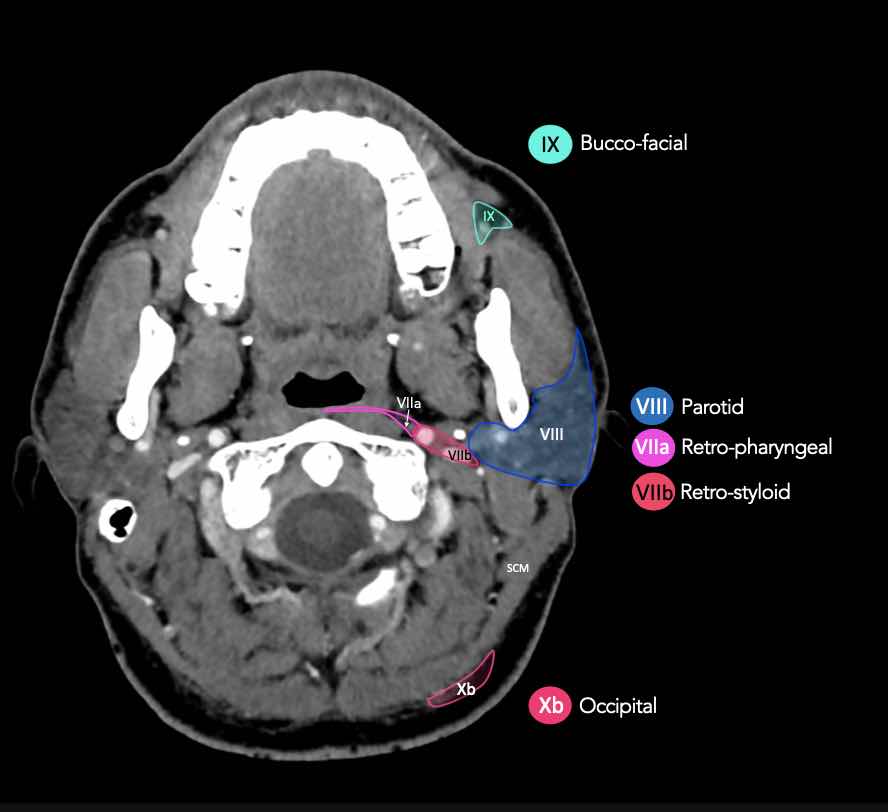

CT Scan Mặt Cắt Ngang (Axial CT)

Các lát cắt CT mặt phẳng ngang tương ứng với hình minh họa tổng quan.

Các lát cắt CT mặt phẳng ngang với hình ảnh chi tiết hơn.

Nhấp vào hình ảnh để phóng to.